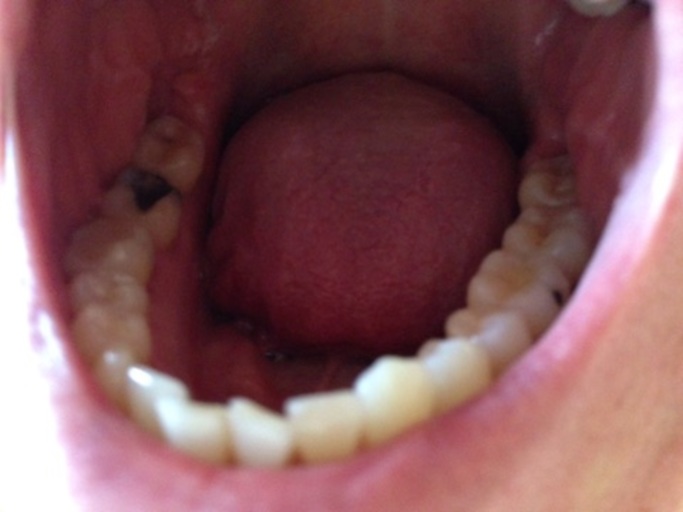

Pain after filling

Hi Doctor, Two months back I got two cavities filled. From past few days, I've pain in lower deep on left side (first or second molar, if I understand the terminology correct). I guess one of the filling is the reason. It started after having half ripened red apple. It started with sensitivity in that area and now its painful. I feel the pain whenever I chew hard foods. I neither smoke nor eat non-vegetarian food. Any advise on this? Thanks, Sandeep

There could be a few things going on. If the pain is only when you are eating hard foods, the filling may be too high. You can go to dentist that did the work and have them check the occlusion.They will have you bite on a piece of paper and if it is high a color will show up indicating its high. If it is they will smooth it down. If this does not slove the issue, have them take an xray of the area. They may not have removed all the decay before placing the filling. In this case the doctor will need to open the filling back up and remove what is in there still. IF the decay was close to the nerve area they may need to place a "special" type of medicine to protect from sensitivity,before placing the filling as well.